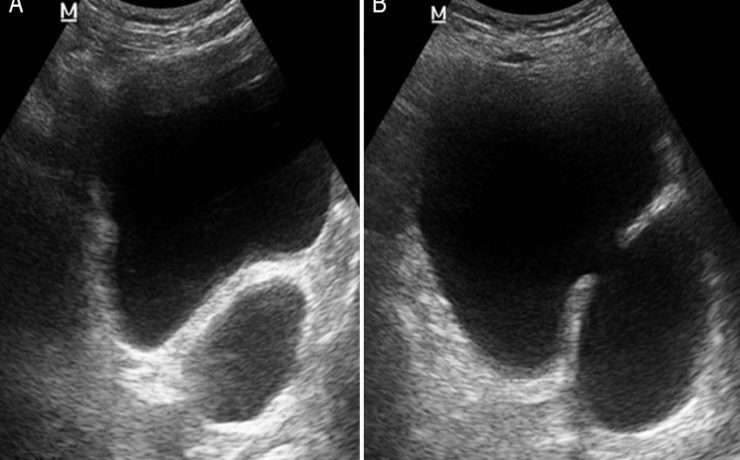

Nódulo de tiroides

La glándula tiroides es con frecuencia afectada por diferentes patologías de tipo funcional y orgánico, que conllevan a cambios funcionales y estructurales de este órgano. Cuando estos cambios son estudiados por medios radiográficos, arrojan una serie de imágenes características que contribuyen con una de las funciones médicos sociales más importantes,